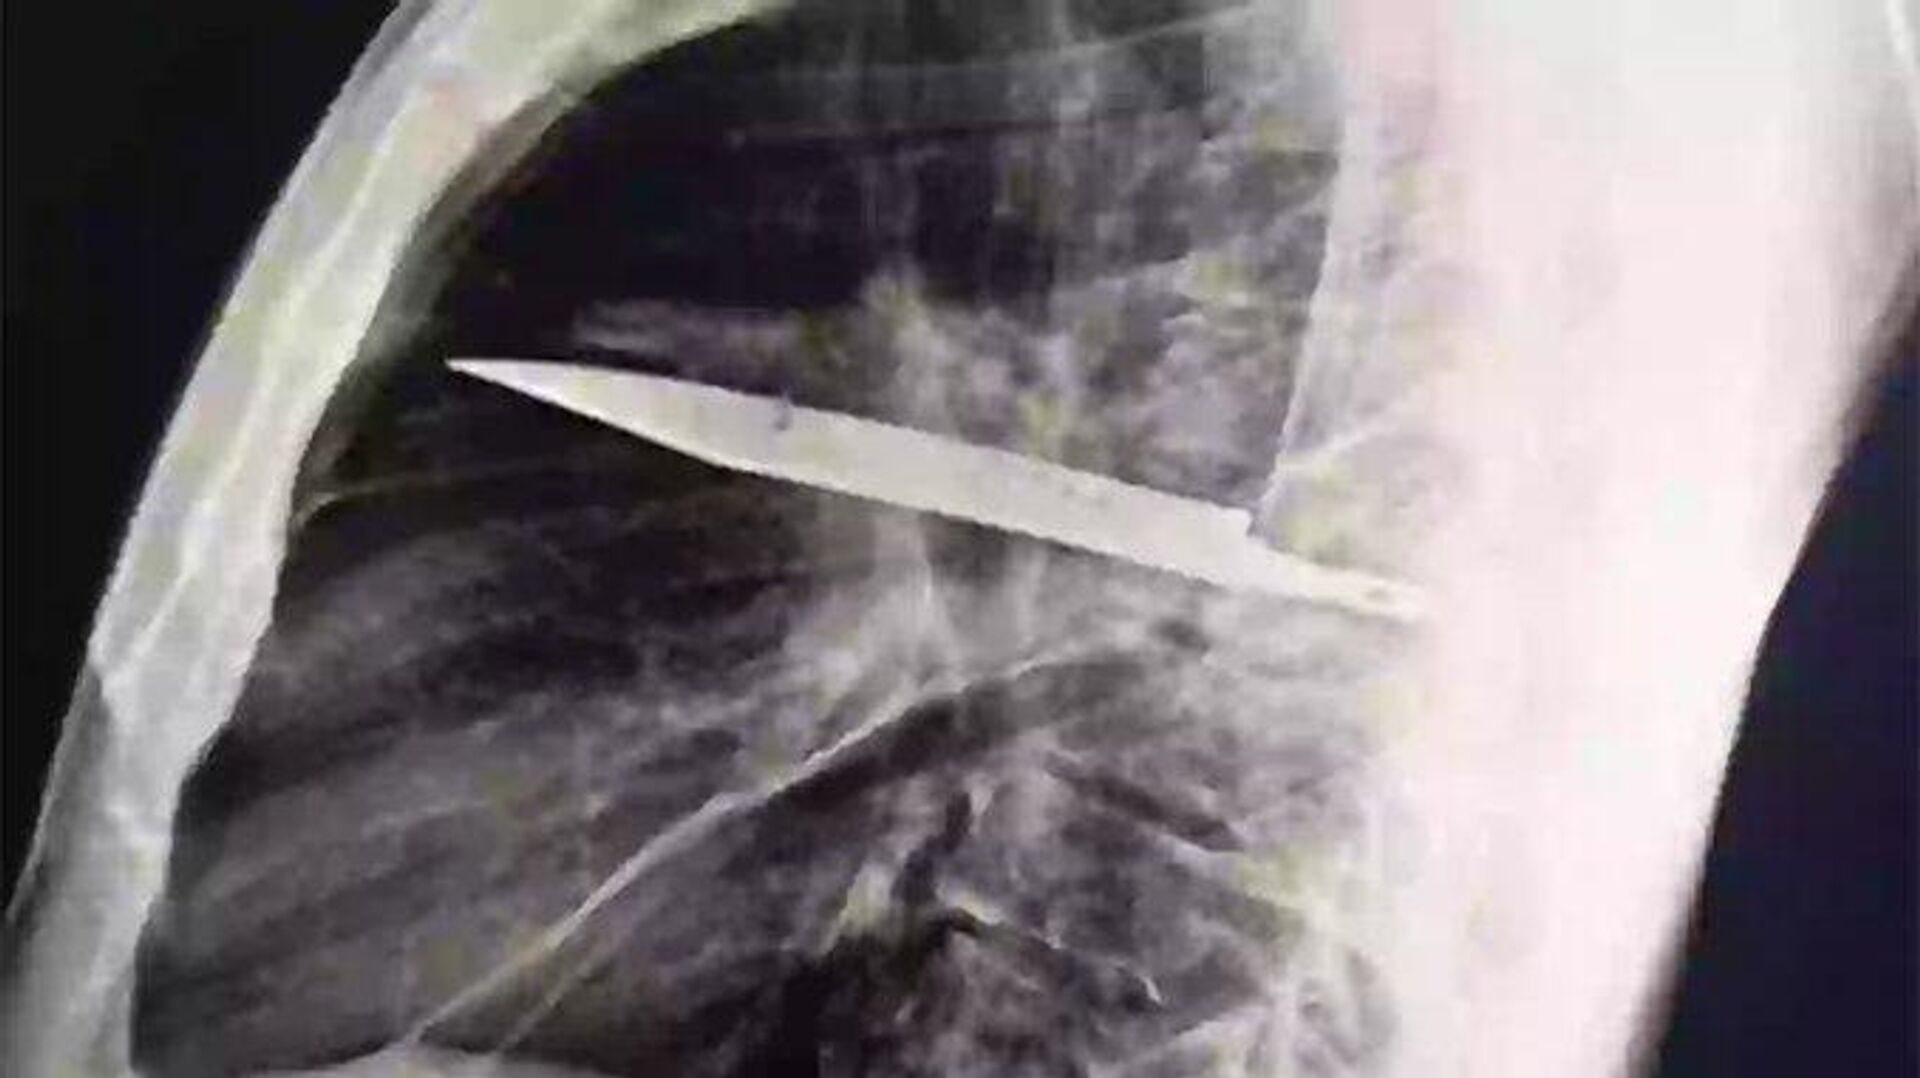

13:58 20.08.2025 (güncellendi: 14:53 20.08.2025) Tanzanya’da 44 yaşındaki bir adam, göğsünden irin gelmesi üzerine hastaneye gitti. Yapılan röntgen, inanılması güç bir gerçeği ortaya çıkardı. Göğsünde sekiz yıldır saplı bir bıçak olduğu anlaşıldı.

Tanzayalı 44 yaşındaki Adam, sağ göğsünden irin akmaya başlayınca enfeksiyon kaptığını düşündü. Ancak doktorlar muayene sırasında durumun çok daha farklı olduğunu fark etti. İlk başta sağlıklı görünen adamın röntgeninde göğsünde büyük bir bıçak tespit edildi.

Hasta, doktorlara sekiz yıl önce bir kavgaya karıştığını ve vücudunun birçok yerinden kesikler aldığını anlattı. O dönem uzak bir bölgede yaşadığı için yalnızca yüzeysel tedavi gördü ve hiç röntgen çektirmedi. Olayın ardından yıllarca göğsünden irin akana kadar hiçbir belirti göstermedi.

Doktorlar hemen ameliyat kararı aldı. Bıçak başarıyla çıkarıldı ve adam sadece 10 gün içinde taburcu edildi. Uzmanlar bunun büyük bir şans olduğunu belirterek, 'Bu kadar uzun süre bıçakla yaşamak ölümcül sonuçlar doğurabilirdi' dedi.

Tıp uzmanlarına göre adamın hayatta kalmasının sebebi, vücudunun bıçağı koruyucu bir kapsül içine alarak iltihaplanmayı geciktirmesiydi. Ancak zamanla bu sistem zayıfladı ve irin akmasıyla birlikte ciddi komplikasyonlar başladı.